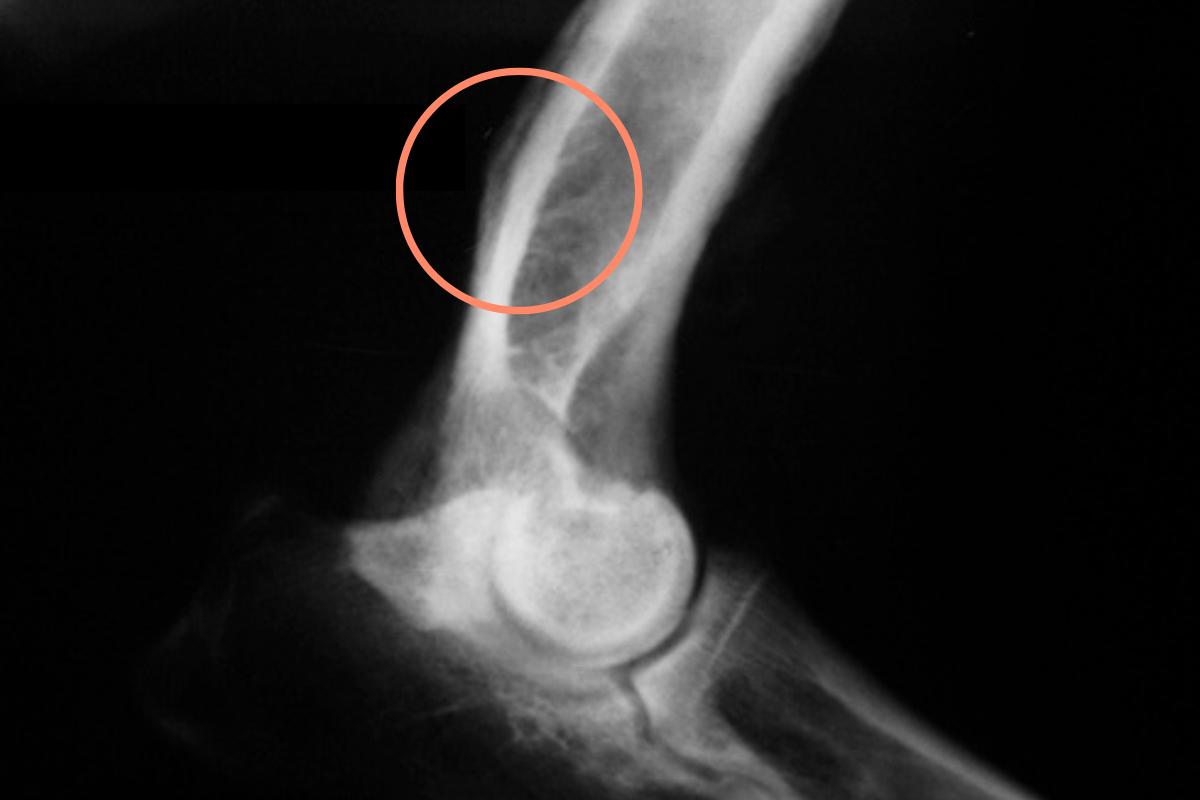

- Radiografía: las lesiones con una imagen de “apolillado”, con márgenes irregulares y mal definidos, especialmente cuando aparecen en las localizaciones más frecuentes de este tumor, nos hacen sospechar de la existencia de un osteosarcoma. Además, mediante la radiografía en ocasiones pueden observarse fracturas, puesto que un pequeño porcentaje de perros con osteosarcoma pueden presentar fracturas patológicas, es decir, fracturas originadas a raíz del daño óseo causado por el tumor. Cabe mencionar que las pruebas por imagen permiten realizar un diagnóstico presuntivo, pero para alcanzar el diagnóstico definitivo es necesario realizar las siguientes pruebas.